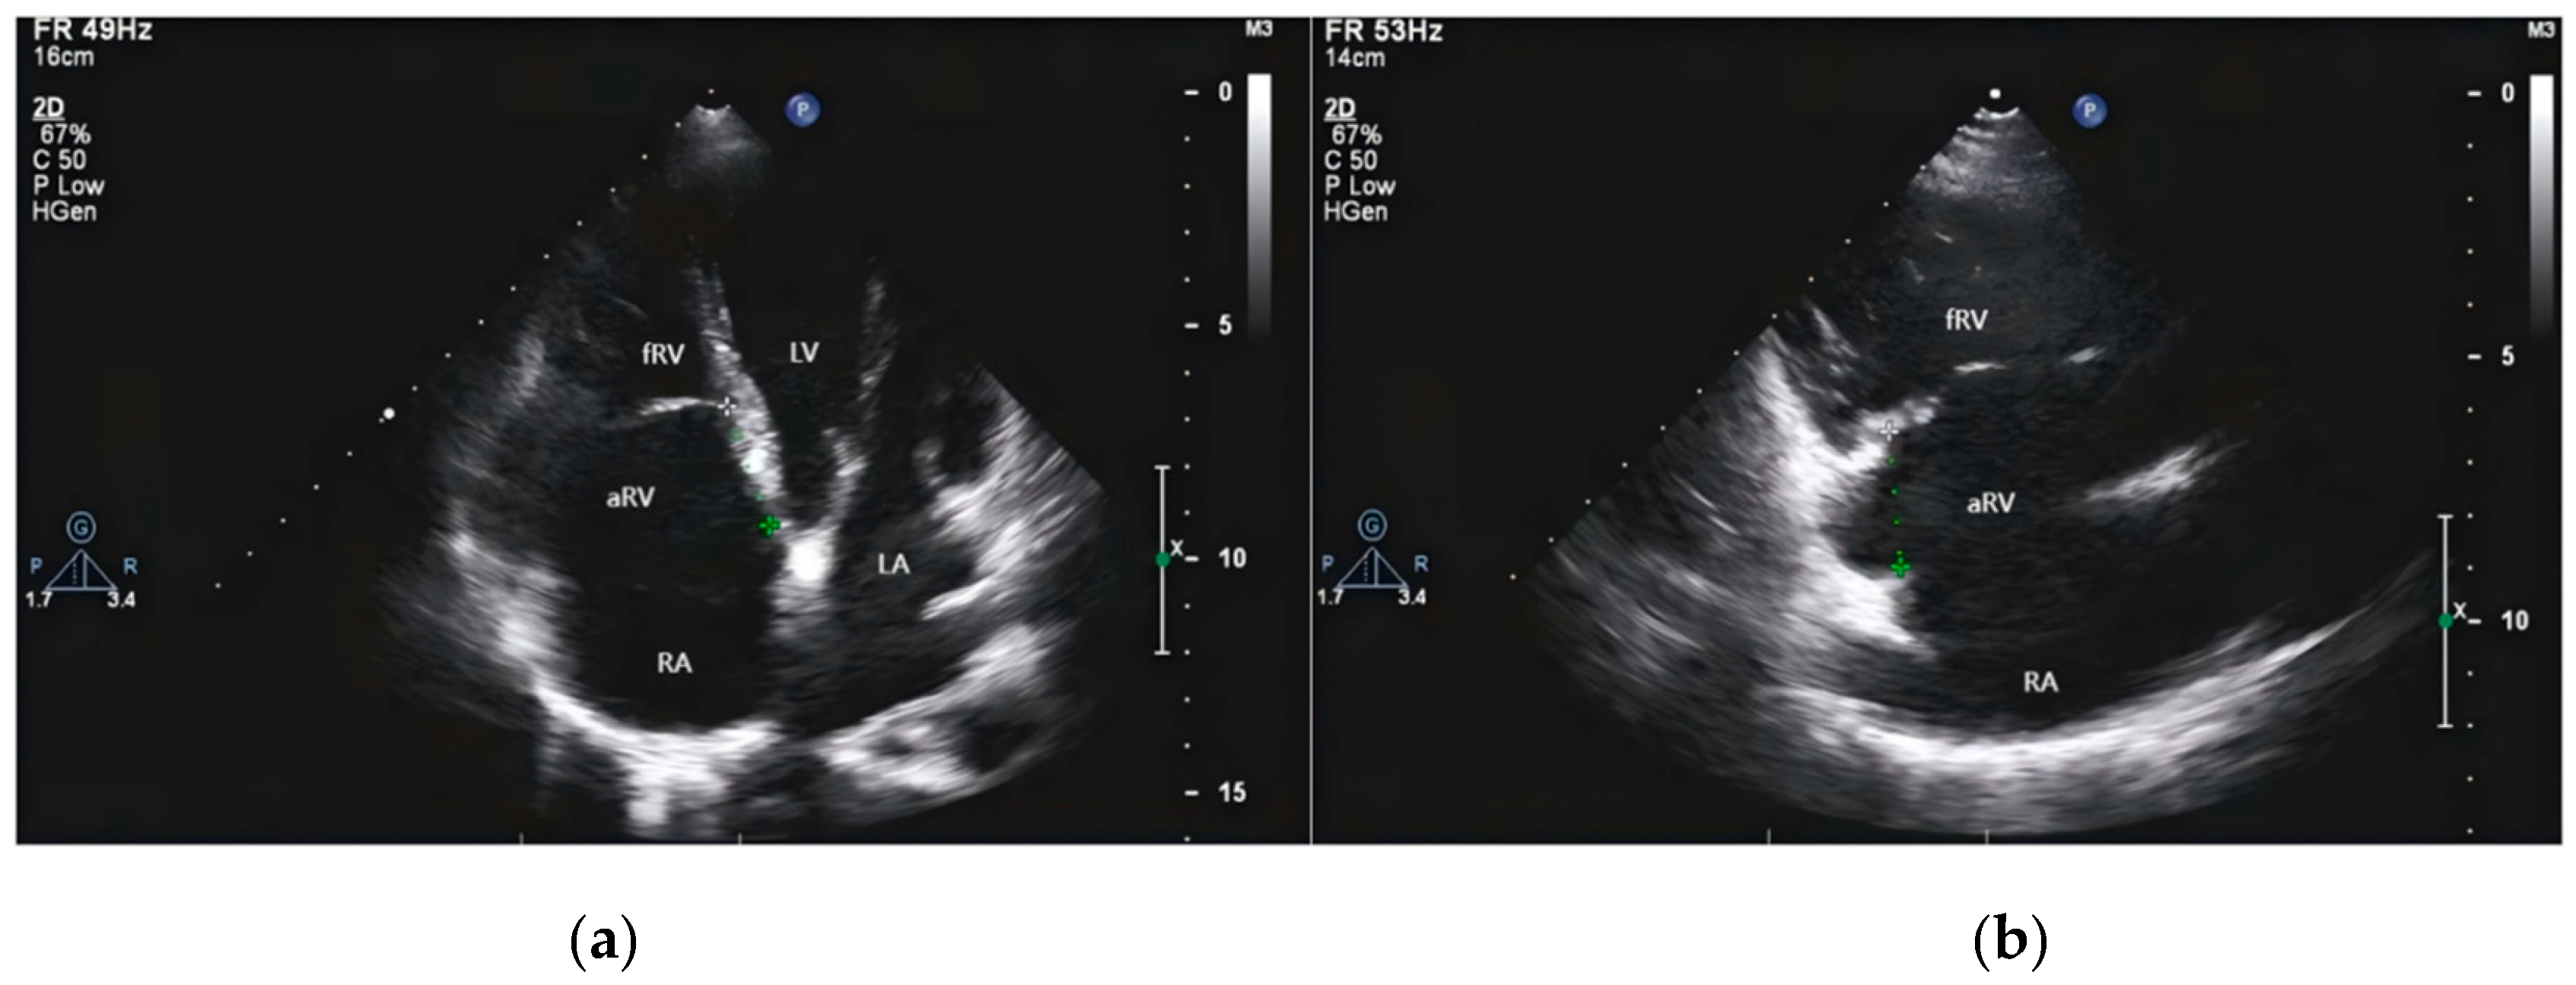

Cardiologists performed all preoperative and postoperative two-dimensional echocardiographic measurements. The dataset included examinations conducted three months prior to surgery, immediately before discharge after surgery, and three months postoperatively. The three-month follow-up echocardiograms were specifically utilized to track temporal changes in right ventricular function. The tricuspid valve was typically evaluated in the apical four-chamber view and inflow tract of RV view, see Fig. 2 below. The long diameter of the right atrium is defined as the distance from the midpoint of the tricuspid valve annulus to the roof of the right atrium at end-systole, when the right atrium is maximally dilated. Similarly, the long diameter of the RV is defined as the distance from the midpoint of the tricuspid valve annulus to the apex of the RV at end-diastole, when the RV is maximally filled. These measurements are taken in the apical four-chamber view. Fifteen patients with EA were randomly selected for reproducibility assessment. For intra-observer variability, the same investigator analyzed the samples at least one month later and was blinded to the initial results. For inter-observer variability, another investigator, who was blinded to the clinical data and results, analyzed the same samples. Patients were classified as having RVD if they met both of the following criteria in pre-discharge echocardiography: RV-FAC less than 35% and TAPSE less than 17 mm.

Figure 2: Transthoracic echocardiography of EA. (a) Four-chamber section shows two-dimensional images of dilated right atrium (RA), atrialized right ventricle (aRV), functional right ventricle (fRV) and the distance between the anterior mitral valve and the tricuspid septal valve. (b) The section of the inflow tract of the two cavities of the right ventricle shows the enlarged RA and aRV, and the posterior tricuspid valve is short and obviously moved downward.